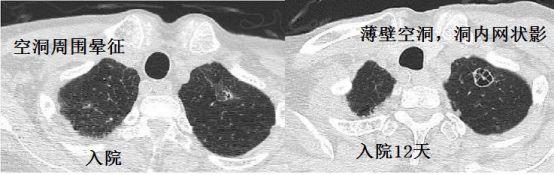

例4:老年男性,因类风湿关节炎口服激素,有慢阻肺病并且长期吸烟,近期发热

入院后给予甲强龙500mg冲击治疗。结果,病情加重。

图6 胸部CT

图6 胸部CT支气管肺泡灌洗液培养:曲霉菌。

空洞周围晕征,空洞内条索影,提示曲霉菌病。